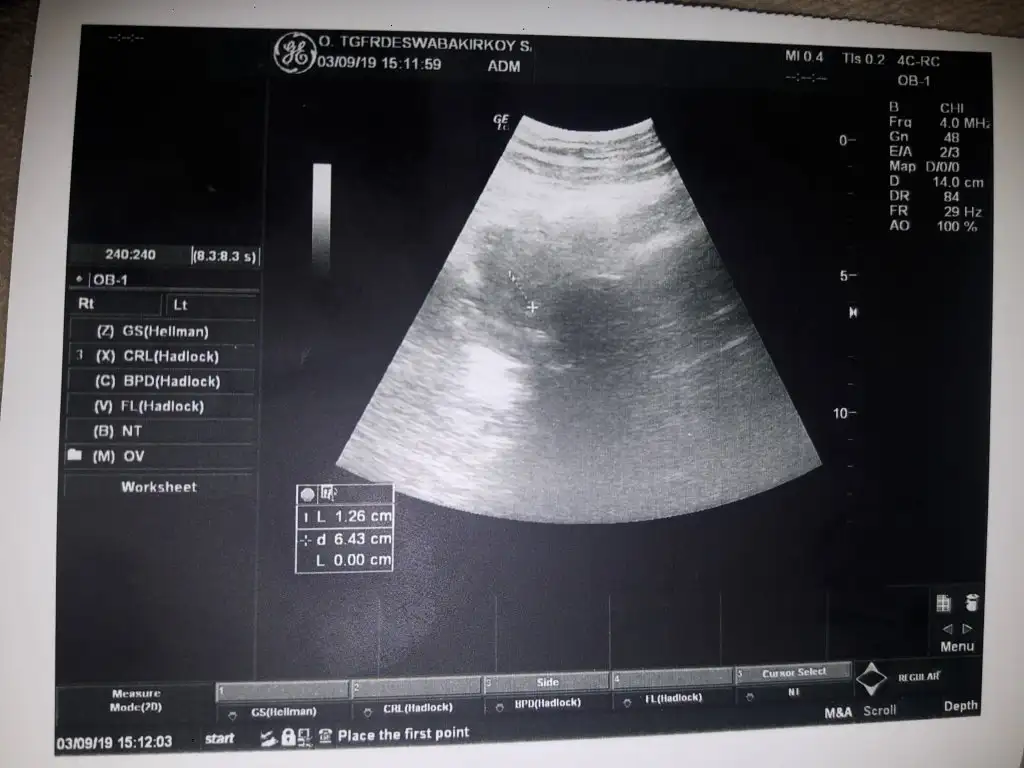

Hamileliğimi öğrendiğimde aşı için bugüne randevu verilmişti, sağlık ocağına gittim. El doppleriyle bebeğin kalp atışını da dinliyolarmış, öyle denedi,böyle denedi,bastırdı,büktü duyamadı. Ben bebeği hissetmesem korkudan ölürdüm ama daha sabah içerde dans ediyodu, onu düşündüm sakin olmaya çalıştım. Kasıklarıma o kadar bastırdı ki asıl ondan sonra korkmaya başladım. Neyse ordan çıkıp doktoruma gittim. Muayane olmak aklımda yoktu olmuş oldum. Bebek iyi her şey yolunda, baştan topuğa 20cm olmuş,250 gr kendisi..